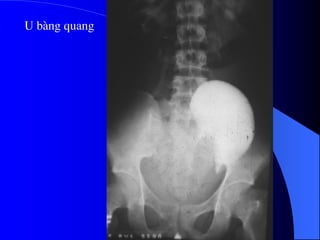

U bµng quang

4.2. U bãøtháûn, niãûu quaín vaì baìng quang * Laì loaûi u biãøu mä âæåìng dáùn niãûu aïc tênh, chiãúm 6-10% caïc u tháûn aïc tênh. Caïc yãúu täú nguy cå chênh laì soíi tiãút niãûu, nhiãùm truìng, nghiãûn thuäúc laï, duìng quaï nhiãöu thuäúc phenacetin. Hay gàûp > 50tuäøi, nam = 2næî. * U laình tênh: polyp, hay gàûp âäü tuäøi 20-40. * U aïc tênh: chuí yãúu Carcinome tãú baìo chuyãøn tiãúp (85%), ngoaìi ra Carcinome tãú baìo vaíy (15%). Di càn ung thæ âãún âæåìng dáùn niãûu hiãúm gàûp. * U âæåìng dáùn niãûu hay gàûp theo thæï tæû åí baìng quang, bãø tháûn, niãûu quaín.

- NÂTM + Âäúivåïi thãø thám nhiãùm coï hçnh aính heûp, båì khäng âãöu, thæåìng gáy æï næåïc. + Âäúi våïi thãø suìi, coï hçnh khuyãút saïng trong âæåìng dáùn niãûu, båì coï thãø khäng âãöu, coï thãø gáy æï næåïc âæåìng dáùn niãûu phêa trãn. Cáön phán biãût våïi cuûc maïu âäng vaì soíi KCQ. ٠Soíi vaì maïu cuûc di chuyãøn vë trê, coï viãön caín quang bao quanh. ٠Maïu cuûc thay âäùi hçnh daûng theo thåìi gian. ٠U âæåìng dáùn niãûu (bãø tháûn, niãûu quaín, baìng quang) coï hçnh aính chán baïm vaìo thaình, nåi khäng coï viãön TCQ bao quanh u.

- Siãu ám Khoïcháøn âoaïn u bãø tháûn, niãûu quaín nãúu khäng coï æï næåïc âaìi bãø tháûn niãûu quaín. U baìng quang trãn siãu ám tháúy hçnh tàng ám trong baìng quang coï næåïc tiãøu räùng ám. Siãu ám coï thãø tháúy mæïc âäü xám láún thaình baìng quang vaì ngoaìi thaình baìng quang.